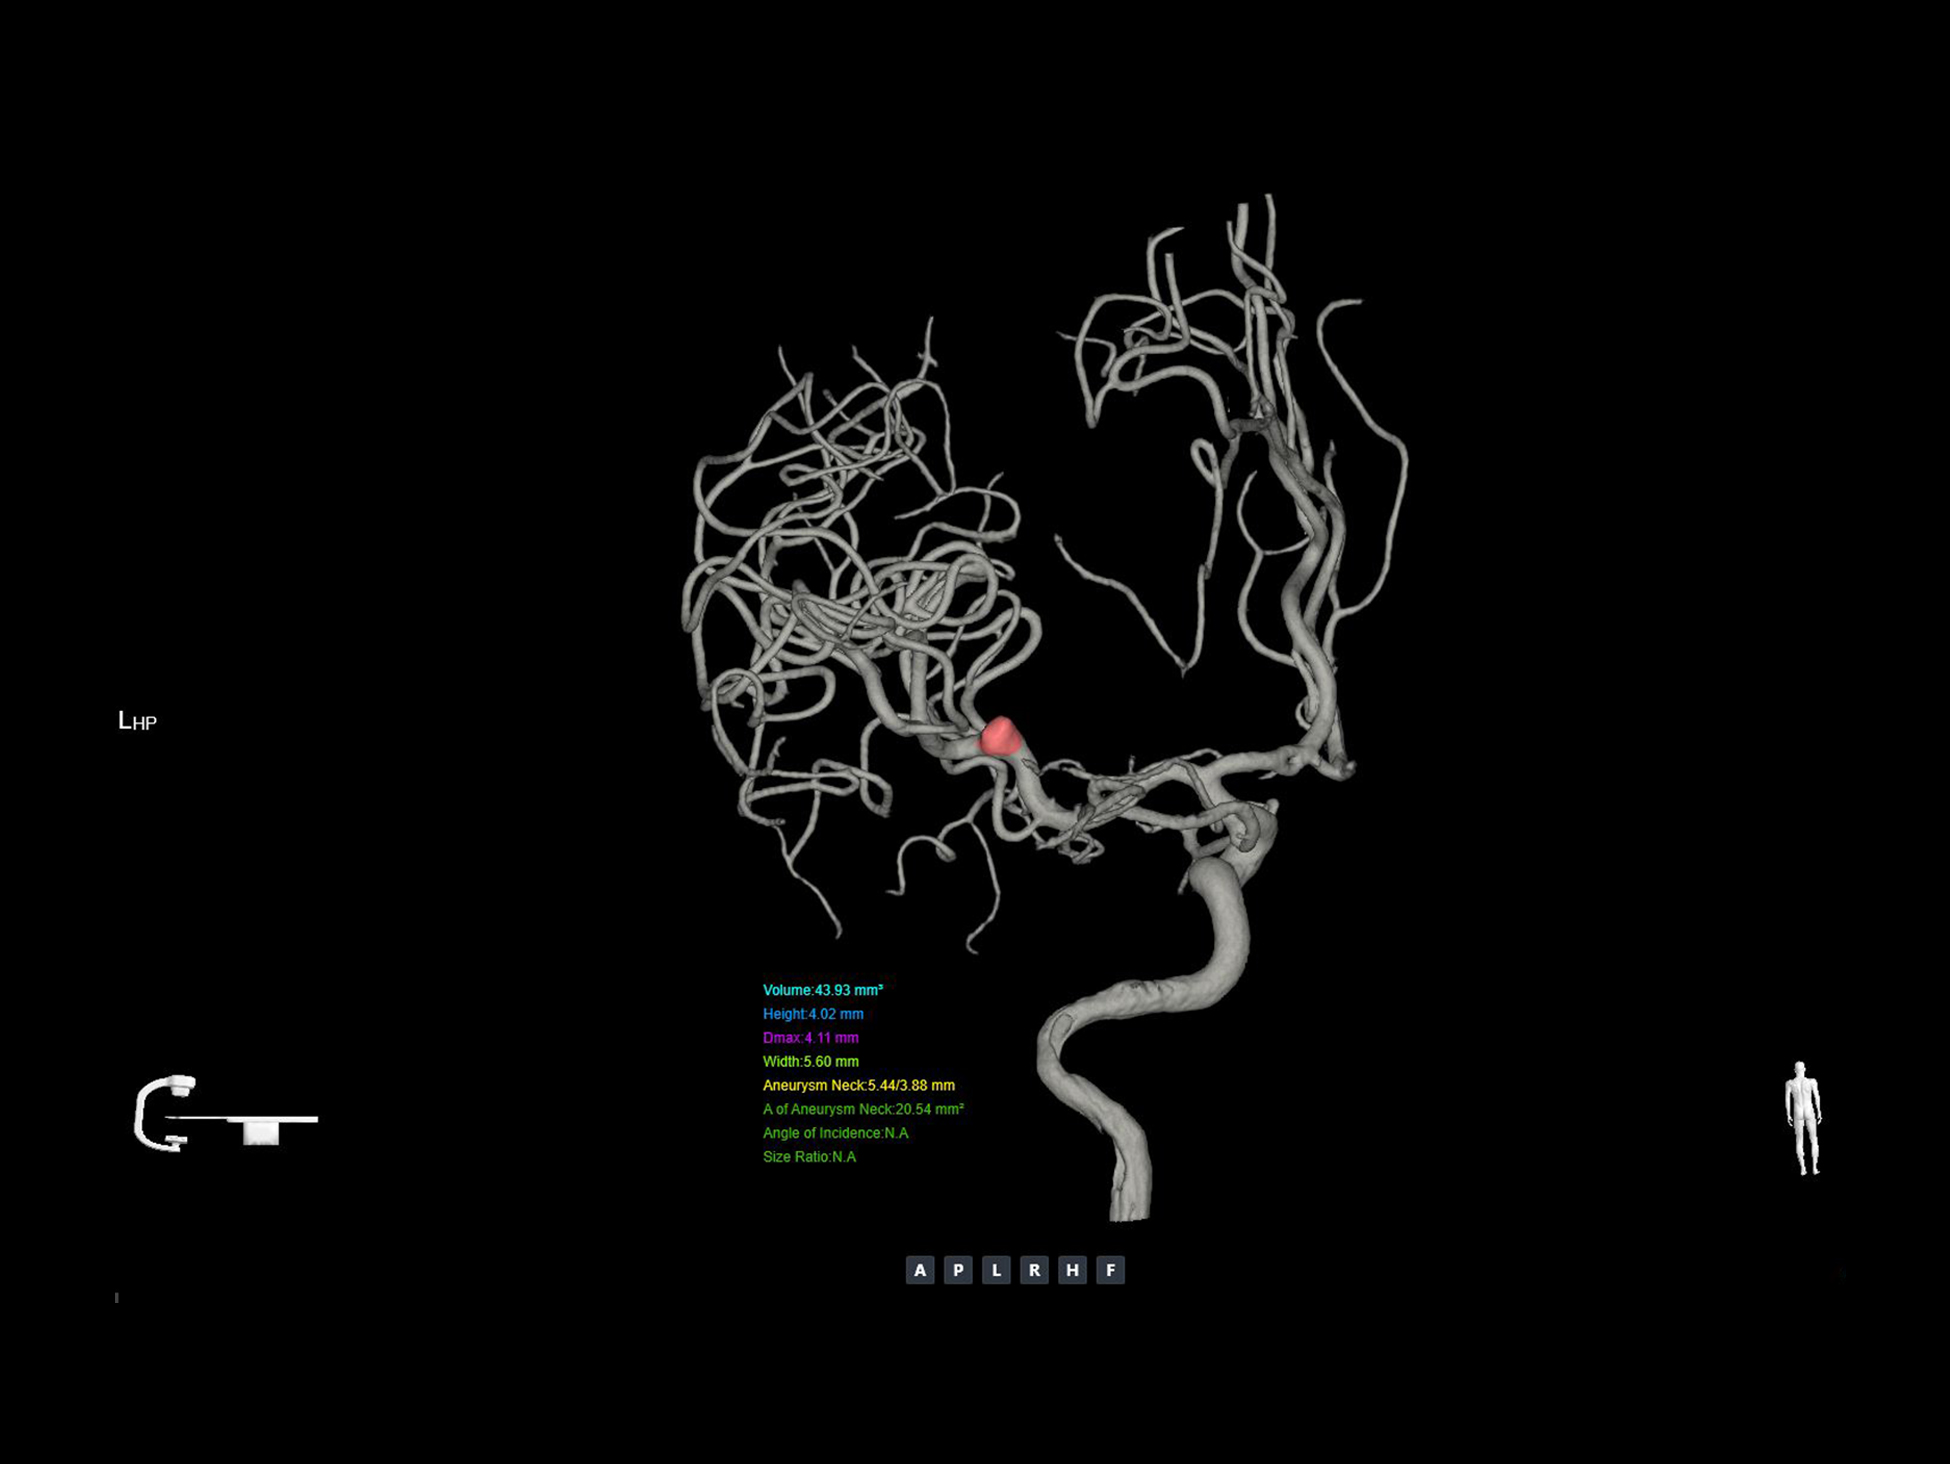

Analiză 3D a anevrismelor*

Permite o analiză cantitativă precisă a anevrismelor pe imagini 3D, oferind informații detaliate despre dimensiune și parametrii esențiali, pentru a sprijini medicii în planificarea optimă a tratamentului bazată pe date.

uVera IQ DSA

uVera IQ DSA oferă imagini de o claritate excepțională, evidențiate în imaginile post-embolizare cu coil, unde se observă clar absența scurgerii de substanță de contrast în interiorul anevrismului.